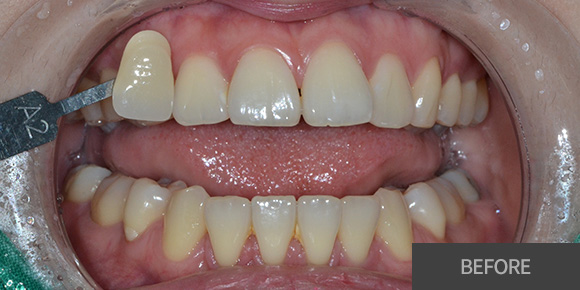

심미레진

전체미백